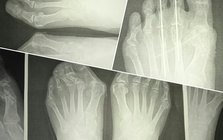

Hallux valgus

靴の健康被害、外反母趾。

外反母趾の問題は痛みだけではありません。